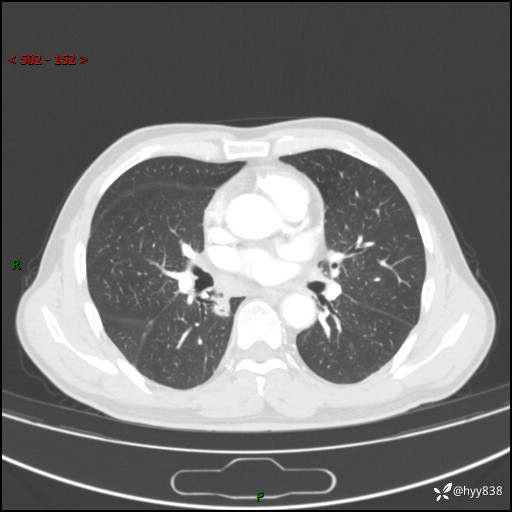

69岁/男,发现肺部病变6天。该有的征象都有,肉芽肿 VS 肿瘤,一念之间---(有结果)

主诉:发现肺部病变6天。

现病史:患者6天前于我院泌尿外科住院,住院期间行胸部CT检查,提示“肺部病变”,患者无畏寒、发热、盗汗、咳嗽、咳痰、咯血、胸痛、呼吸困难,无反酸、腹痛、腹泻、头痛、头晕等不适。未予特殊处理,现为进一步诊治,门诊以“肺肿物”收入我科。 患者本次起病以来,精神食欲尚可,大小便正常,体力及体重无明显变化。

胸部CT平扫+增强